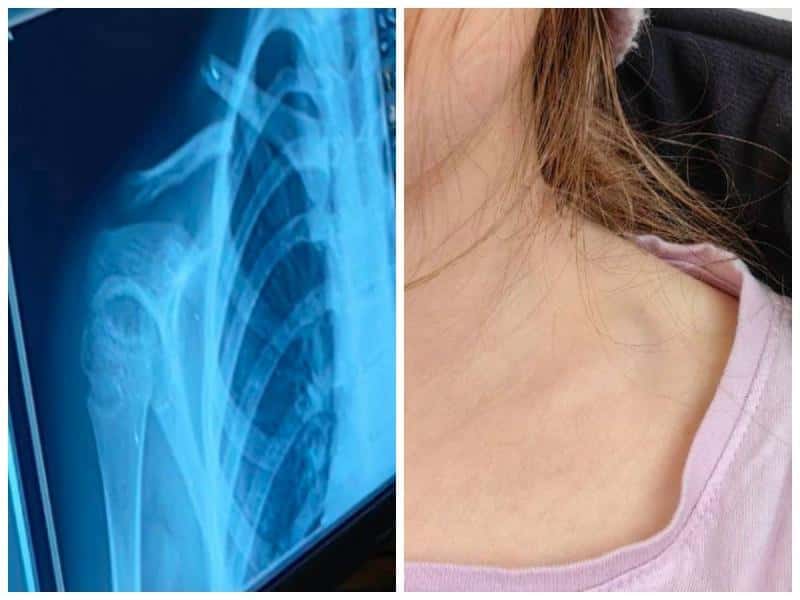

Школьница сломала ключицу на батуте в Каменске-Уральском: конфликт с владельцем игрового зала решен миром

В Каменске-Уральском школьница получила травму во время празднования дня рождения в одной из городских игровых комнат. Девочка прыгала на батуте и упа...